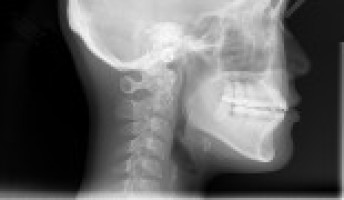

When a patient with head and neck cancer has surgery to remove it, they often need reconstructive surgery in the form of a “free flap”, which is skin and tissue taken from a different part of the body and connected to the blood vessels of the wound in need of repair.

This free flap method, called microvascular reconstruction, carries around a 10-40% risk of wound complications, with 10% of cases requiring another surgery.

A Michigan Medicine study finds that early postoperative CT scans and MRIs can help predict whether a flap will fail, which could allow surgeons to intervene earlier.

Currently, most surgeons use ultrasound to assess viability for free flap reconstruction with techniques known as doppler and skin paddle.

Those methods often are unable to evaluate deeper aspects of the flap, or air and blood products cause interference in visualisations, which affects how well clinicians can analyse a flap’s viability, says Srinivasan, who is also a clinical professor of radiology at U-M Medical School.